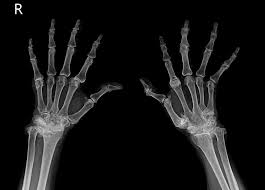

류마티스 관절염 진단 과정

류마티스 관절염의 진단은 여러 가지 방법으로 이루어집니다. 일반적으로 혈액 검사와 엑스레이, 염증 수치를 통해 진단을 받습니다. 혈액 내 류마티스 인자 및 항CCP 항체 검사로 류마티스 관절염을 확진할 수 있습니다. 진단 과정은 환자의 병력과 증상을 기반으로 하며, 전문의가 적절한 검사 방법을 선택하여 진행합니다. 이러한 진단 과정을 통해 류마티스 관절염인지 여부를 정확하게 판단할 수 있습니다.